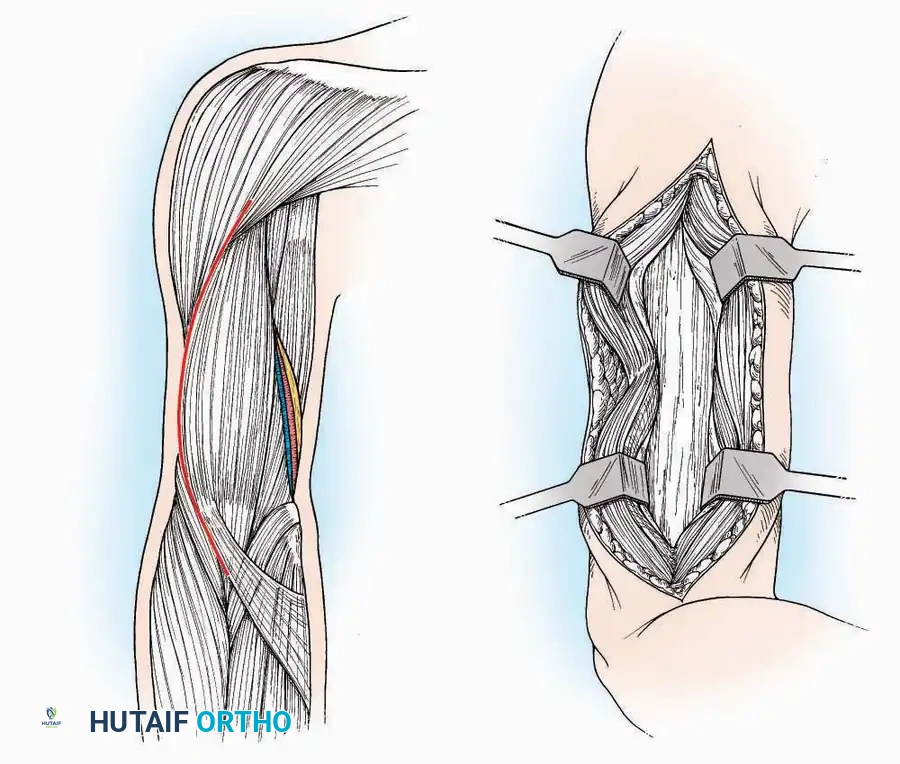

Lateral Approach (Extensile Lateral)

This is the workhorse approach for open reduction and internal fixation (ORIF) of displaced intra-articular calcaneal fractures.

Indications: ORIF of calcaneus fractures, lateral wall exostectomy, subtalar arthrodesis.

Positioning: Lateral decubitus with the operative leg up, or supine with a large bump under the ipsilateral hip to internally rotate the leg.

Surgical Technique:

* Incision: Begin the incision on the lateral margin of the Achilles tendon near its insertion. Extend it distally to a point 4 cm inferior and 2.5 cm anterior to the lateral malleolus. (For trauma, a classic L-shaped extensile incision is often used, dropping straight down anterior to the Achilles, then curving gently toward the base of the 5th metatarsal).

* Superficial Dissection: Divide the superficial and deep fasciae. It is imperative to create a "full-thickness" flap containing skin, subcutaneous fat, and periosteum to prevent flap necrosis.

* Nerve Protection: The sural nerve crosses the proximal and distal limbs of this approach. It must be identified and protected within the anterior flap.

* Deep Dissection: Isolate the peroneal tendons (longus and brevis). Incise and elevate the periosteum below the tendons to expose the lateral wall of the calcaneus.

* Tendon Management: If severe deformity or infection is present, the peroneal tendons may be divided via Z-plasty and repaired at the conclusion of the case, though this is rarely necessary in modern fracture care.